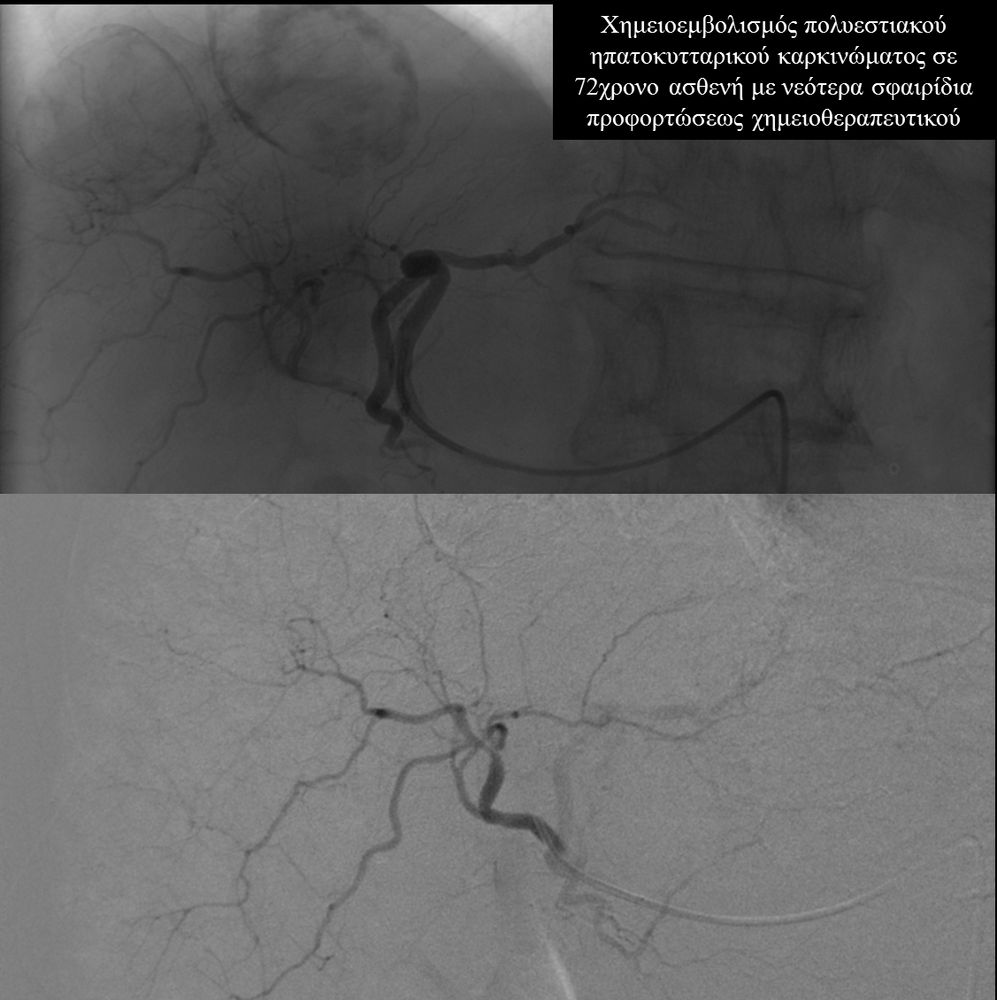

Ο χημειοεμβολισμός έχει καθιερωθεί σαν θεραπεία εκλογής στο ενδιάμεσο στάδιο του ηπατοκυτταρικού καρκινώματος.

Ο χημειοεμβολισμός είναι γενικά καλά ανεκτός και οι σοβαρές επιπλοκές είναι εξαιρετικά σπάνιες.Οι περισσότεροι ασθενείς μπορούν να επιστρέψουν στο σπίτι τους μία ημέρα μετά τη θεραπεία.